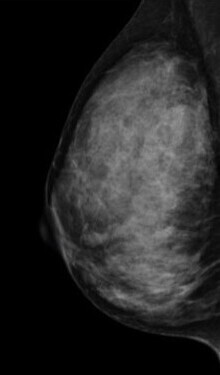

検査結果では、乳房の構成を以下4つに分類してお知らせします。

1.脂肪性

2.乳腺散在

3.不均一高濃度

4.極めて高濃度

3・4に該当する乳房は「高濃度乳房(デンスブレスト)」と呼ばれ、乳腺が白く映るためマンモグラフィのみでは異常が隠れてしまうことがあります。

そのため、マンモグラフィ検査と乳腺超音波検査の併用を強くおすすめします。

症状がなくても、高濃度乳房と判定された方は積極的な併用検診が早期発見につながります。